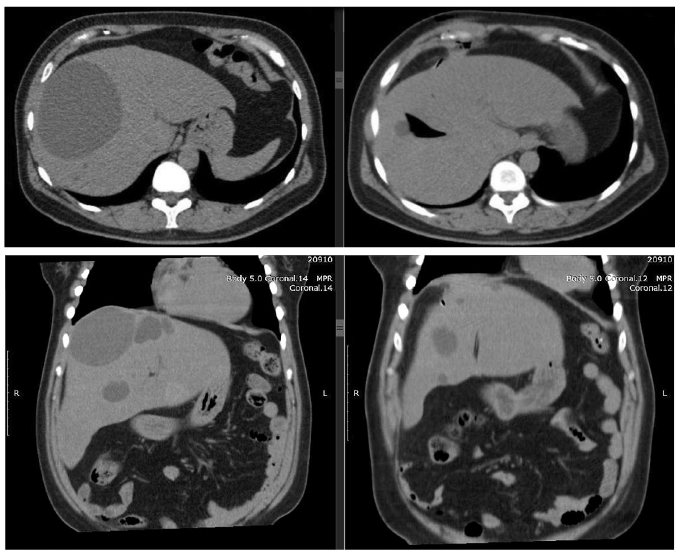

Se realizó una tomografía de abdomen que informó hígado de tamaño normal, contornos regulares, con imágenes hipodensas de contornos bien definidos con densidad de agua (8 UH), dispersas en el lóbulo derecho e izquierdo; la de mayor tamaño mide 114 x 94 x 105 mm en el segmento hepático VIII y otras de menor tamaño que miden entre 10 y 20 mm en el segmento II y VII; no hay dilatación de las vías biliares, ni lesiones de aspecto metastásico, colecistectomía. (Figura 3).

El tratamiento con el que se inicia es el drenaje percutáneo del quiste hepático de mayor tamaño (114 x 94 x 105 mm en el segmento hepático VIII), utilizando guía tomográfica y técnica de Seldinger; se obtienen 300 cc de líquido seroso y se deja catéter de 8 french a nivel del quiste (Figuras 4 y 5). Una semana después del procedimiento se realiza la escleroterapia (alcoholización) del quiste, procedimiento que se lleva a cabo en quirófano bajo sedación y utilizando ecografía y fluoroscopía: a través del catéter de instila contraste hidrofílico y con ayuda de fluoroscopía se comprueba que el quiste no tiene comunicación con la vía biliar (Figura 6); paso seguido se introduce a través del catéter alcohol de 70 grados durante un minuto y se retira el alcohol. Con ayuda ecográfica se comprueba la indemnidad de la vía biliar; luego de cinco días se retira el catéter. La evolución clínica es favorable, con alivio completo de los síntomas después de la intervención.